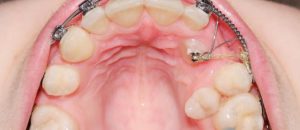

Применение винтов в практике ортодонта

Современный ортодонтический винт — это малая система по выравниванию зуба в правильное положение, используют как дополнительные атрибут.